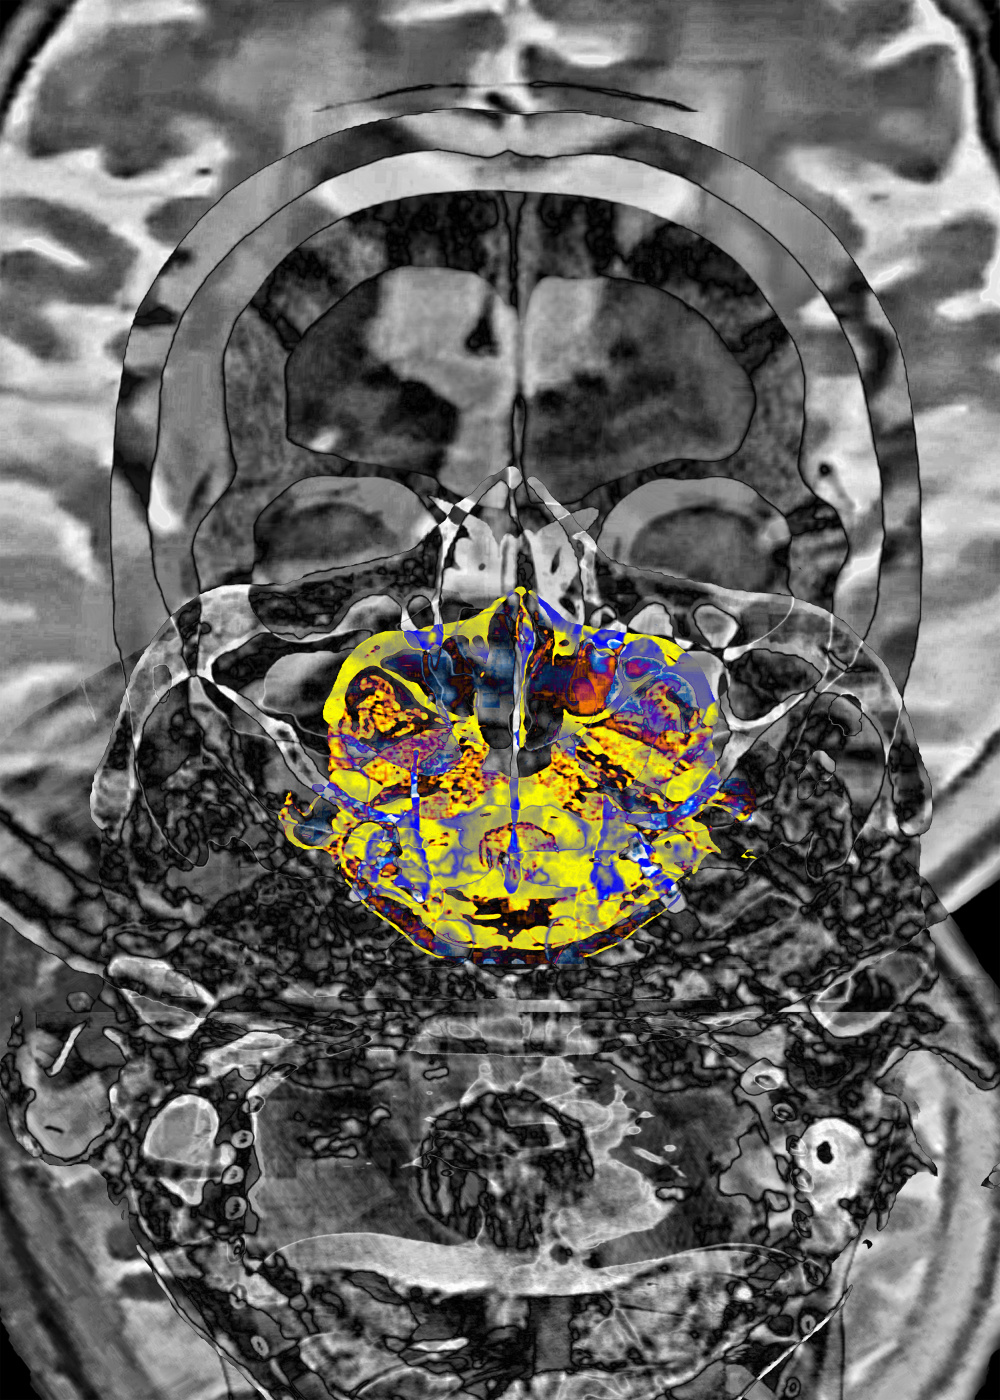

Stroke is due to partial blood circulation disturbance in the brain, resulting in partial loss of body function. When the right hemisphere of the brain is stroke, there will be left side defects. On the contrary, left hemisphere stroke is right paralysis or partial paralysis. This work is mainly designed based on the brain images of CT scan and MRI, emphasizing the thinking space of the brain and controlling people's behavior patterns. In this spatial structure, the pathological manifestations of translational medicine are integrated into the left and right inverted images in philosophical thinking.